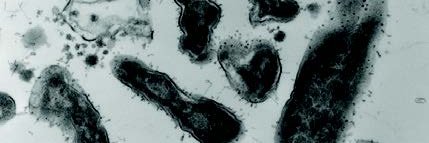

Skin androgens regulate Staphylococcus aureus pathogenicity via quorum sensing dlvr.it/TRCQqx #MicroSky

1/11 Ever wondered why men have more S. aureus infections than women? Check out how testosterone stimulates S. aureus through activation of quorum sensing in our @harristryonlab preprint. Led by M. Sindhura John PhD @UTSWDerm. A #microbiome #staph#mrsa🧵 biorxiv.org/content/10.110…